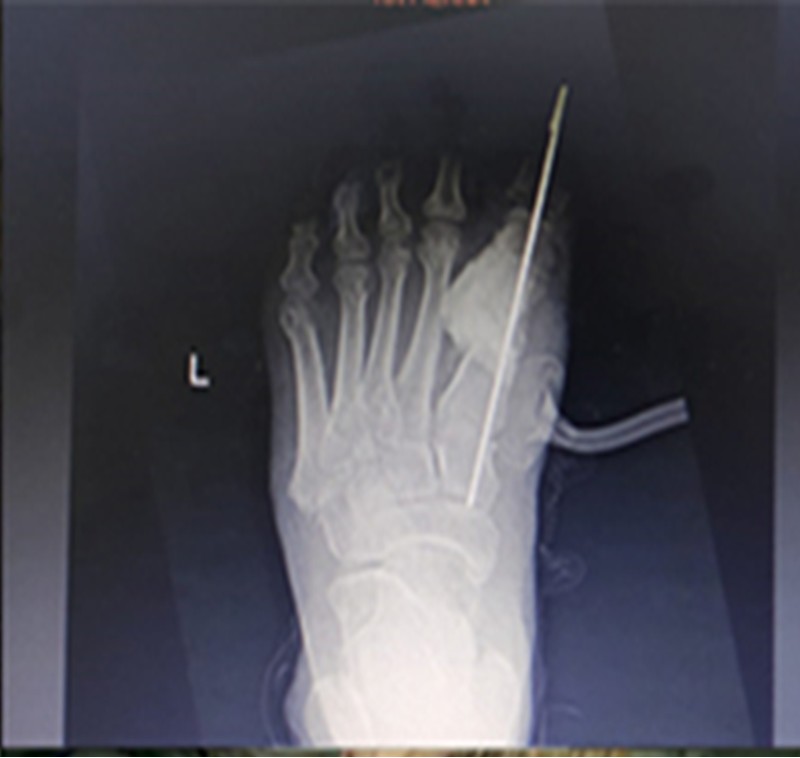

59-летний пациент поступил в отделение гнойной хирургии с жалобами на боли в левой стопе. При осмотре и пальпации был обнаружен отек, связанный с воспалительными изменениями на медиальной и дистальной областях подошвенной поверхности стопы. Проведено комплексное обследование, включая рентгенологическое и КТ стопы. Выявлена деструкция головки и диафиза первой плюсневой кости, а также и проксимальной головки основной фаланги. Результаты соответствующих лабораторных исследований показали, что уровень гликированного гемоглобина (HbA1c) составил 8,2.

Аутологичный трансплантат гребня подвздошной кости считается золотым стандартом в качестве источника костного трансплантата в хирургии по методике Masquelet из-за различных факторов. Основным из них является относительно высокая концентрация мезенхимальных клеток (МСК), которые могут дифференцироваться в другие типы клеточных тканей, включая остеобласты, а также большое количество факторов роста, таких как TGF-B (трансформирующий фактор роста бета) и PDGF (тромбоцитарный фактор). Они играют важную роль в развитии костной ткани и пролиферации костных клеток. Костные трансплантаты фиксировали интрамедуллярно спицей Киршнера. Рану удалось закрыть местными тканями, предварительно дренировав с использованием активной аспирации.

Через 4 недели результаты рентгенологического исследования показали, что трансплантат без признаков лизиса и отторжения. Пациенту разрешили ходить с опорой, используя ортопедическую обувь.

Через 7 месяцев от начала лечения металлический фиксатор удален.

В настоящее время пациент ходит самостоятельно. При контрольном осмотре, лабораторном контроле, КТ и рентгенологическом исследовании область операции без каких-либо воспалительных изменений, выраженные признаки консолидации трансплантата.